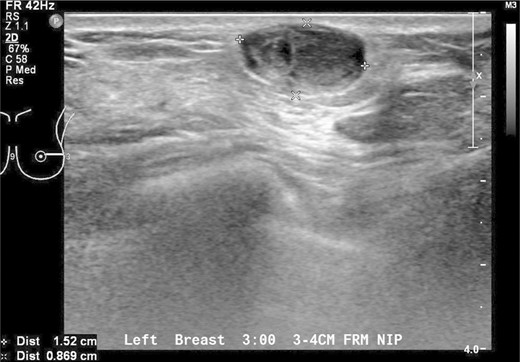

Our patient underwent an excisional biopsy without a preoperative needle biopsy. A 1.2 × 1.2 × 0.8 cm smooth well-encapsulated nodule was removed in entirety from the breast parenchyma. On bisection, the cut section displayed a pale pink smooth homogeneous appearance. Microscopic evaluation showed an encapsulated spindle cell tumour with prominent nuclear palisading and features typical of a schwannoma (Fig. 3). There was also strong and diffuse positive staining of S-100, favouring the diagnosis of schwannoma (Fig. 4). There was no evidence of malignancy in the specimen.

Spindle cell tumour with palisaded arrangement of nuclei, typical of schwannoma. Cellular (Antoni A) areas alternate with looser myxoid (Antoni B) areas.

Macroscopically, breast schwannomas are described as white, grey, tan or pink well-encapsulated masses. Microscopically, they are spindle cell tumours with Antoni A patterns (hypercellular areas with palisading nuclei surrounding pink areas called Verocay bodies) and Antoni B patterns (hypocelluar regions with looser stroma and myxoid change) Schwannomas almost always stain positive for S100 protein. A cytologic diagnosis via fine needle aspiration may be possible if clusters of spindle-shaped cells arranged in a palisading fashion and lacking epithelial elements are seen [3].